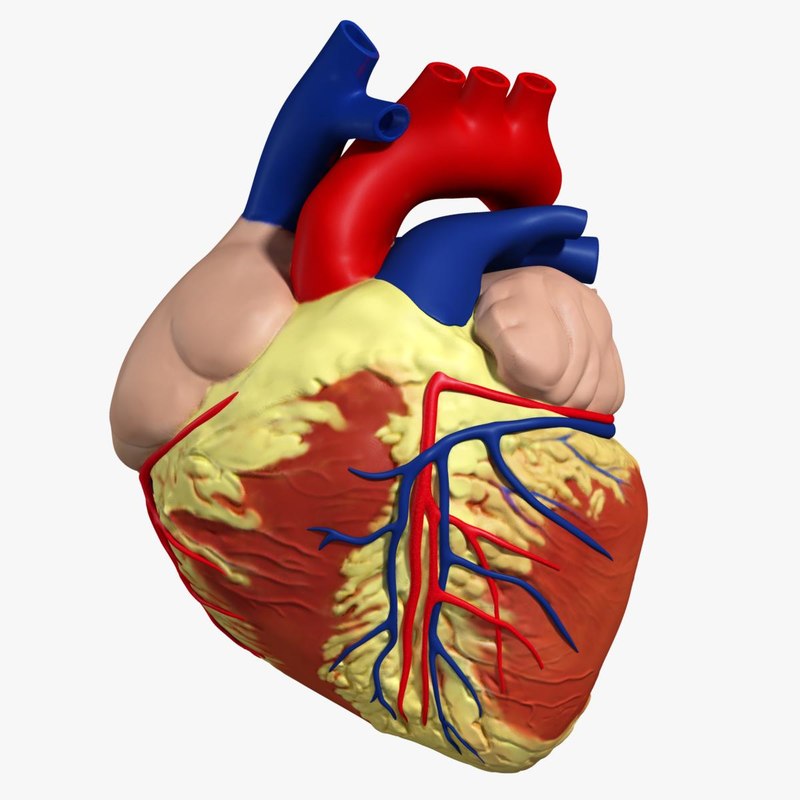

Human Heart Drawing Outline at GetDrawings | Free download  3d anatomy human heart

3d anatomy human heart  Show me a diagram of the human heart? Here are a bunch! - Interactive Biology, with Leslie Samuel

Human Heart Sketchbook study by bluesytealyren on DeviantArt | Human heart drawing, Anatomical  3d human heart

3d human heart  Animated Realistic Human Heart - Medically 3D asset

Animated Realistic Human Heart - Medically 3D asset  Zygote::3D Heart Model | Medically Accurate | Human Anatomy

Zygote::3D Heart Model | Medically Accurate | Human Anatomy  Zygote::Solid 3D Human Heart Model

Zygote::Solid 3D Human Heart Model  3D human heart anatomy model - TurboSquid 1283134

3D human heart anatomy model - TurboSquid 1283134  anatomy human heart 3d c4d